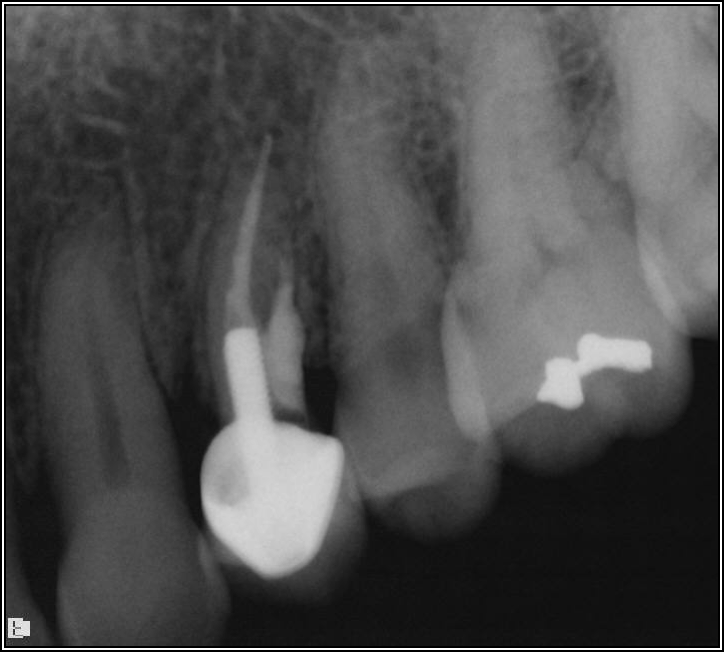

If a tooth stands alone, greater forces will be placed on it because it has no adjacent teeth to provide support. This situation will affect the decision-making process for placing a post. Figure 3 shows a tooth that was on an island and would be having three implants placed in front of it. The tooth would take a much greater beating than another tooth that had support proximally. Even though it had a good root canal, the clinician would need to account for whether the tooth would last until the implants integrated. Figure 4 shows a case that would quickly proceed to implants. The patient had a less-than-ideal bridge for over a decade, with decent endodontics and functionality. There was also an overhang on the premolar. The post was not ideal in this case because there was one distal canal and not all the gutta-percha was removed from it. An intimate fit should be the goal with the post and the walls. Whether using a threaded or non-threaded post, there should not be excess gutta-percha because it is not as solid as the tooth and will lead to greater movement. That movement on the tooth and bridge will create too much force and result in demise.

Fig 4. Case that quickly would proceed to implants.

Figure 4